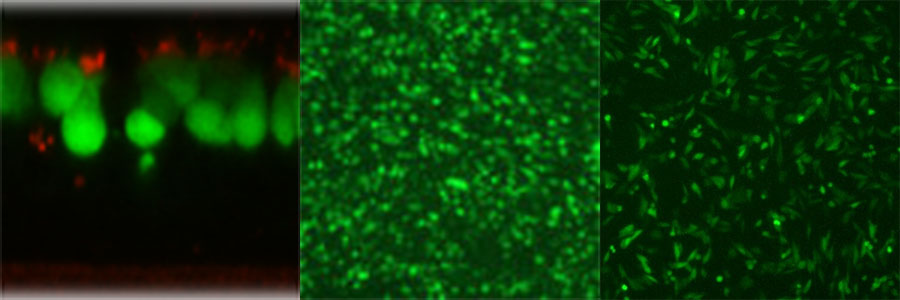

毒株构建方法:为了构建 RSV-GFP1,GFP(Green Lantern Protein,Life Technologies)被设计为位于 RSV 基因起始和基因末端序列的两侧,并作为第一个启动子-近端基因插入野生型 RSV 菌株 A2 抗基因组 RNA 的全长 cDNA 中。RSV-GFP1 是通过将 HEp-2 细胞与抗基因组质粒和 N、P、M2-1 和 L 支持质粒共转染并用表达 T7 RNA 聚合酶的修饰牛痘病毒 MVA-T7 感染它们来挽救的。将获救的病毒在 HEp-2 细胞中扩增,分装并储存在 -80°C 下。 在细胞培养物中,发现 RSV-GFP1 复制到近亲本滴度,并以与亲本病毒相似的速率产生合胞体。使用这种病毒,发现RSV的主要靶细胞类型是人类气道中的纤毛上皮细胞(图)。